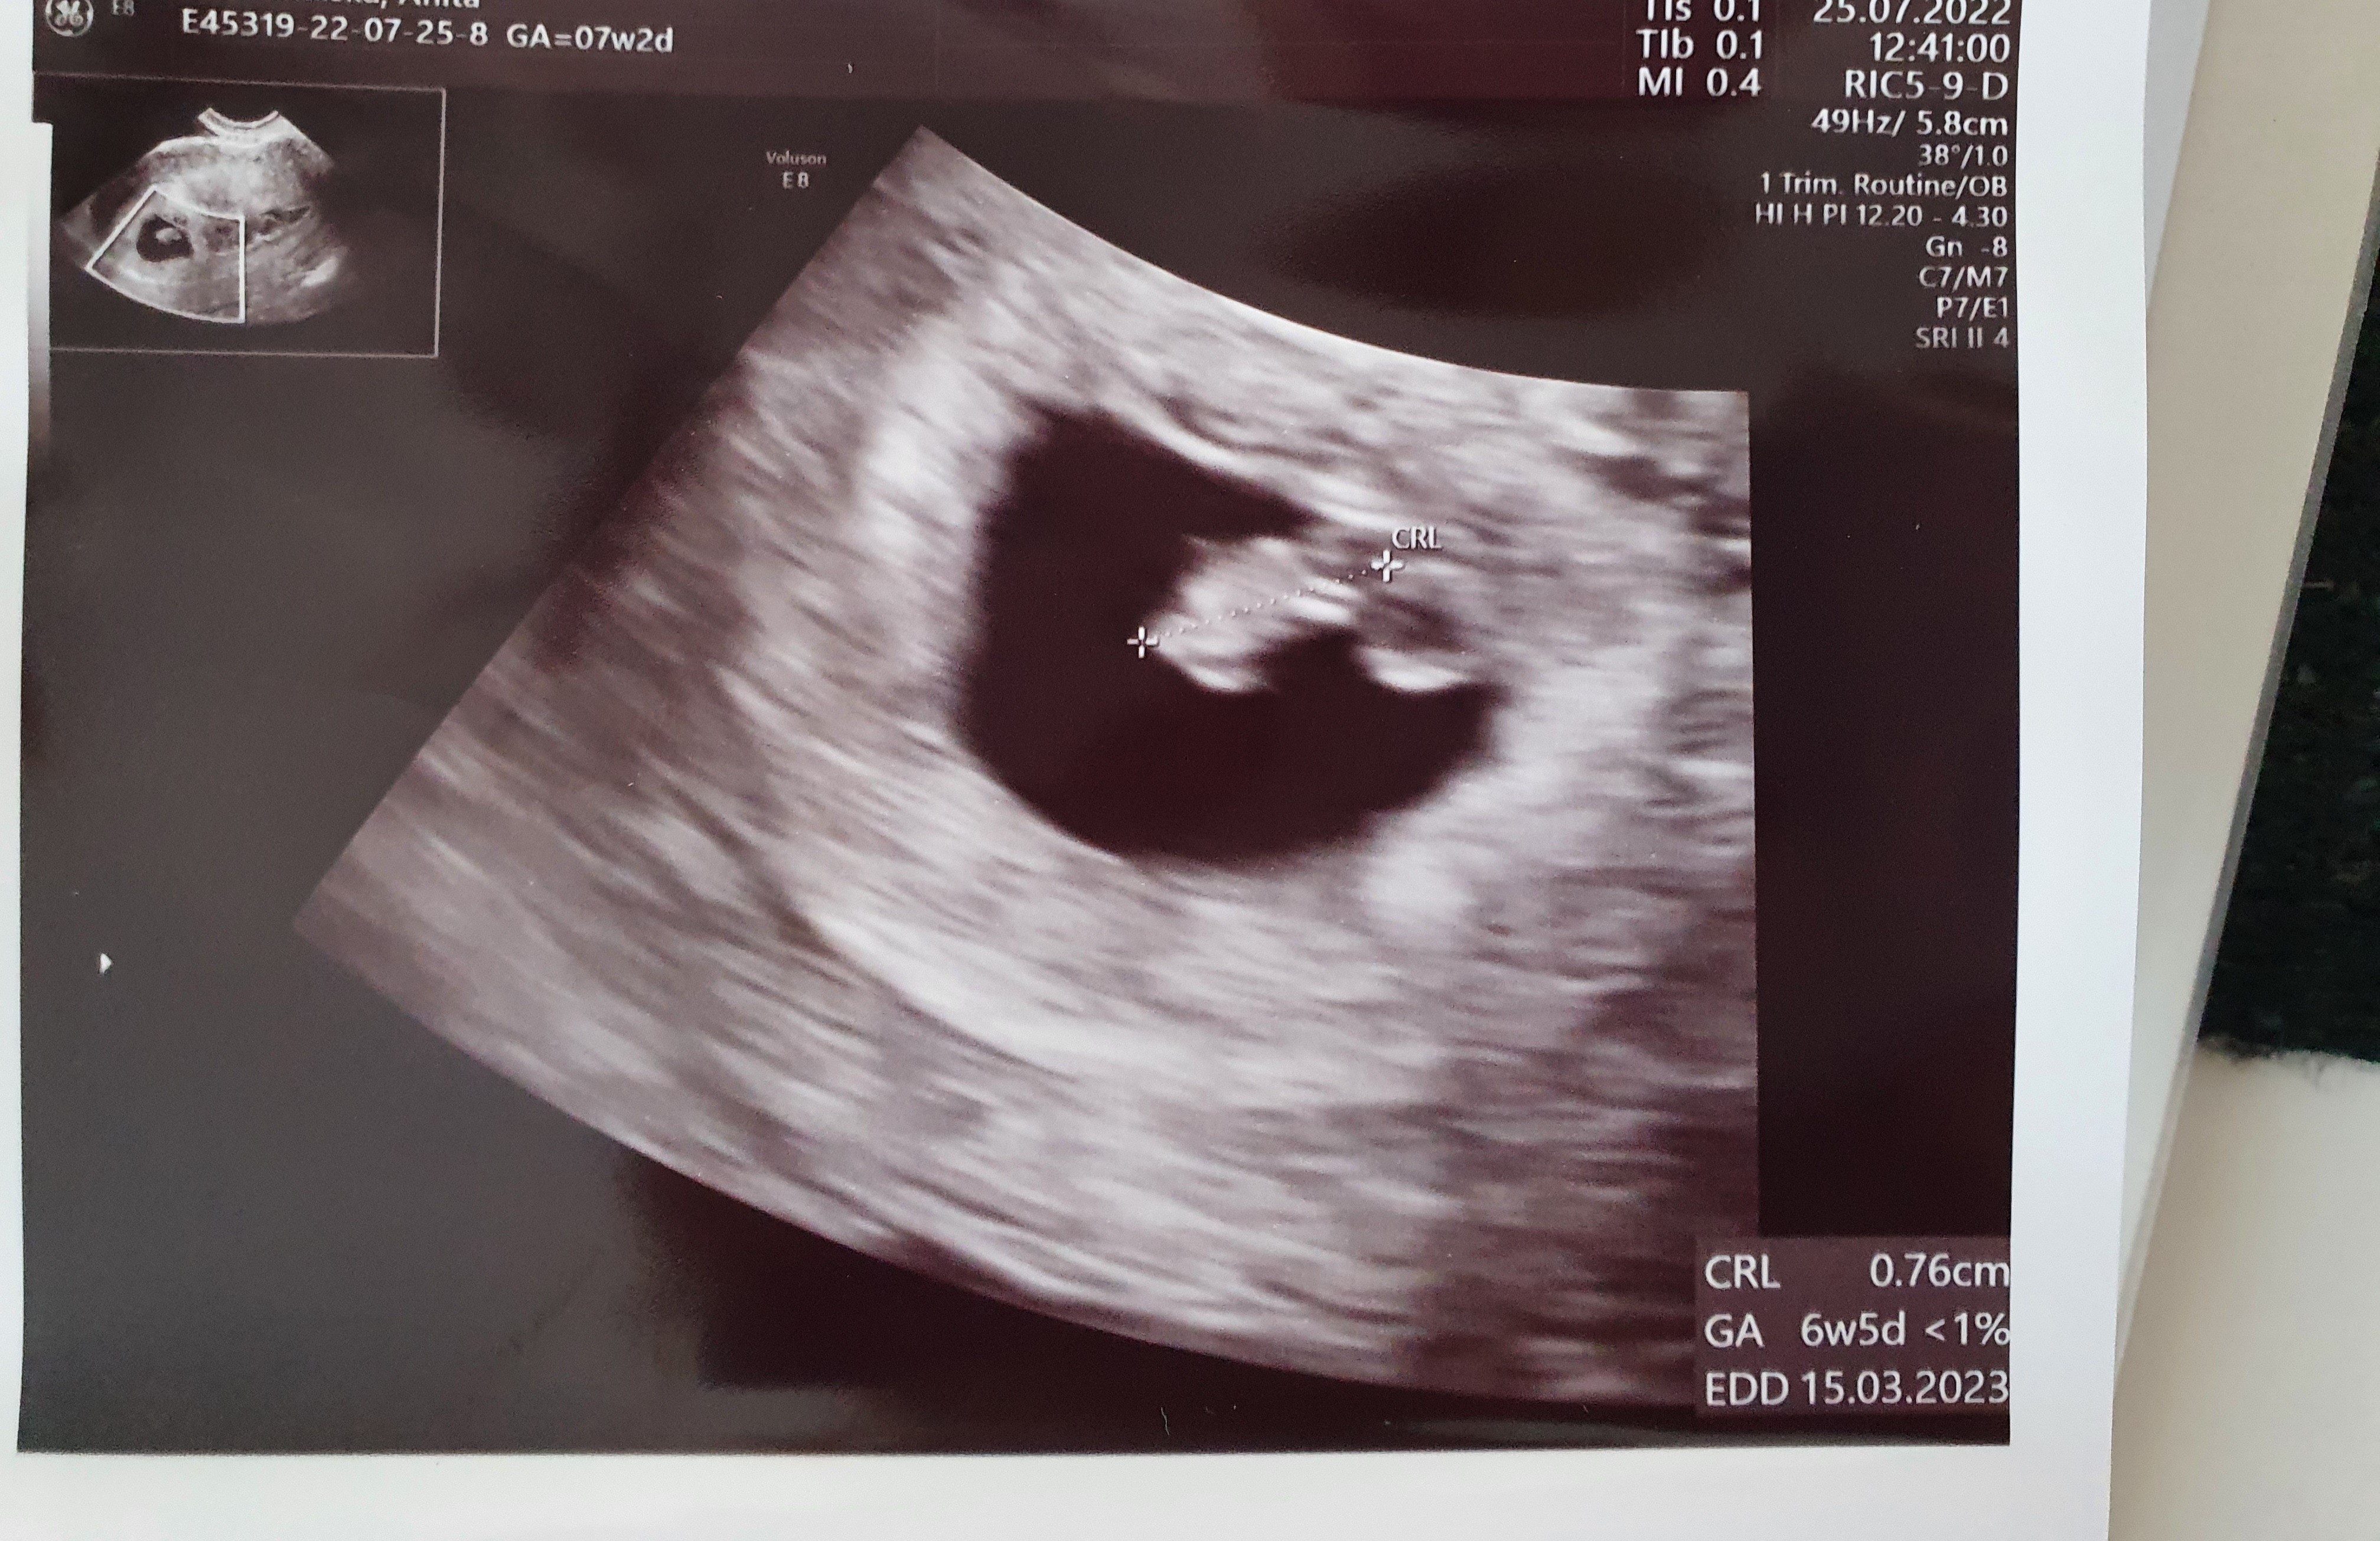

Kurcze mi nie powiedziała, w jakim tempie biję serduszko, a ja byłam taka jakąś zdziczała, że zapomniałam sama zapytać 🤣 byłam w tygodniu 6+5

Noo powiedziala, że jak na ten etap to wszystko dobrze się rozwija :)

W którym tyg miałaś wizytę jak biło 116? U mnie dokładnie tyle samo w 6plus6, ale lekarz skomentował tylko, że rozkręca się, także za miesiąc liczę na takie rozkręcenie jak u Ciebie :)

na tym etapie minimum to chyba 110 takze spokojnie 😊 u mnie też się maluch rozkręcał 😊 ponoć do 9 tyg przyspiesza akcja serduszka a pozniej stopniowo ciutenke się obniża (powiedziała to żeby się nie stresować jak na kolejnym USG będzie niższa wartość) 😊 na pewno będzie wszystko cacy! 😁

• 20220802_161600.jpg

20220802_161600.jpg

1,7 MB · Wyświetleń: 93